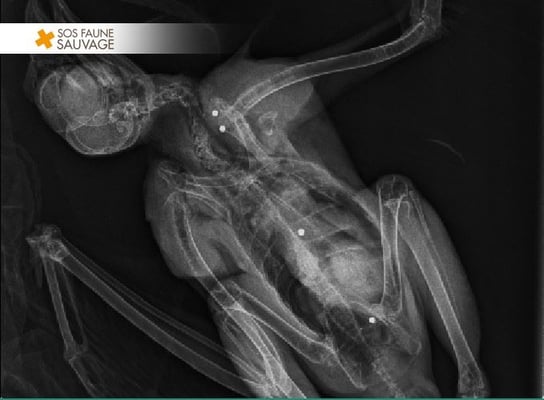

La seconde, une buse variable a eu moins de chance. Les plombs ont perforé ses poumons, entraînant une suffocation lente et douloureuse, nous avons alors dû nous résoudre à pratiquer une

euthanasie.

La quatrième, une chouette hulotte, est décédée 5 jours après son arrivée des séquelles neurologiques causées par un plomb situé dans son crâne.